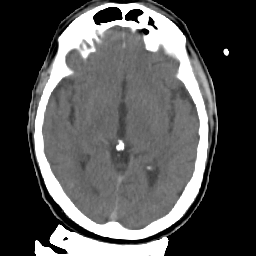

Meningioma: Roentgen-ray CT #2 -- Slice #9

[Home][Help][Clinical] Slice 9